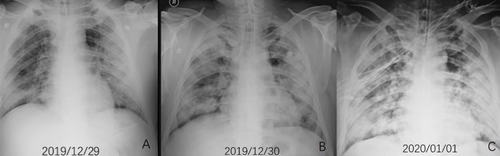

“Typically with ARDS, the lungs become inflamed. It’s like inflammation anywhere: If you have a burn on your arm, the skin around it turns red from additional blood flow. The body is sending it additional nutrients to heal. The problem is, when that happens in your lungs, fluid and extra blood starts going to the lungs. Viruses can injure cells in the walls of the alveoli, so the fluid leaks into the alveoli. A telltale sign of ARDS in an X-ray is what’s called ‘ground glass opacity,’ like an old-fashioned ground glass privacy window in a shower. And lungs look that way because fluid is white on an X-ray, so the lung looks like white ground glass, or sometimes pure white, because the lung is filled with so much fluid, displacing where the air would normally be.”